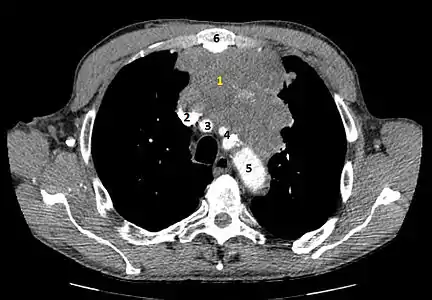

Tomodensitométrie

Le scanner permet de localiser la tumeur dans le médiastin et d'évaluer son extension locale[5]. L'analyse des caractéristiques de la tumeur[8] (taille, tumeur bien limitée ou non, contenu solide, kystique ou graisseux) et la présence de signes associés (nodules pulmonaires, épanchement pleural, syndrome cave supérieur) permet d'orienter le diagnostic. Certaines tumeurs peuvent être identifiées avec précision sur la combinaison du scanner et de l'examen clinique[8] : goître thyroïdien ectopique, thymome, tératome ou kyste bronchogénique ou péricardique. Pour d'autres, une biopsie est nécessaire à l'affirmation du diagnostic[8].